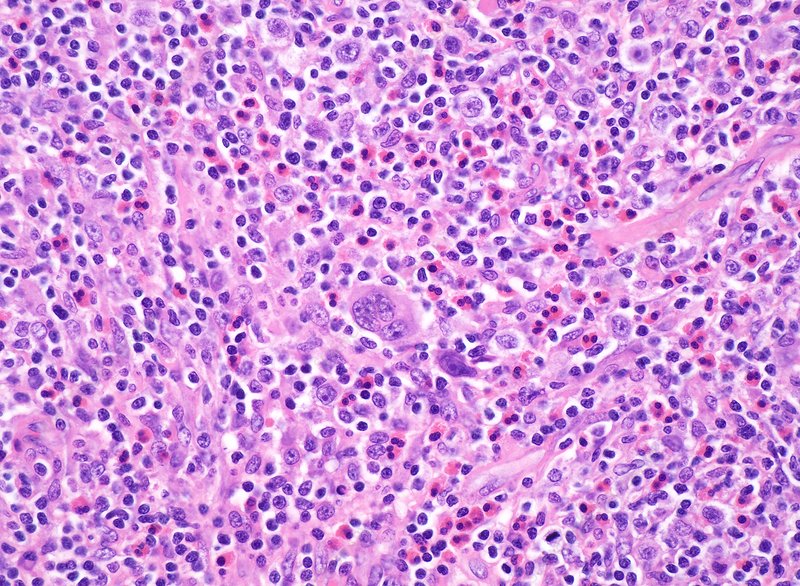

그리고 조직검사가 실시될 수 있습니다.

이것은 비대된 림프절에서 세포를 제거하는 것을 포함합니다.

혈액병리학자로 알려진 의사는 림프종 세포가 있는지 여부와 세포 유형을 결정하기 위해 세포를 검사할 수 있습니다.

혈액병리학자가 림프종 세포를 발견하면 추가 검사를 통해 암이 얼마나 퍼졌는지 확인할 수 있습니다.